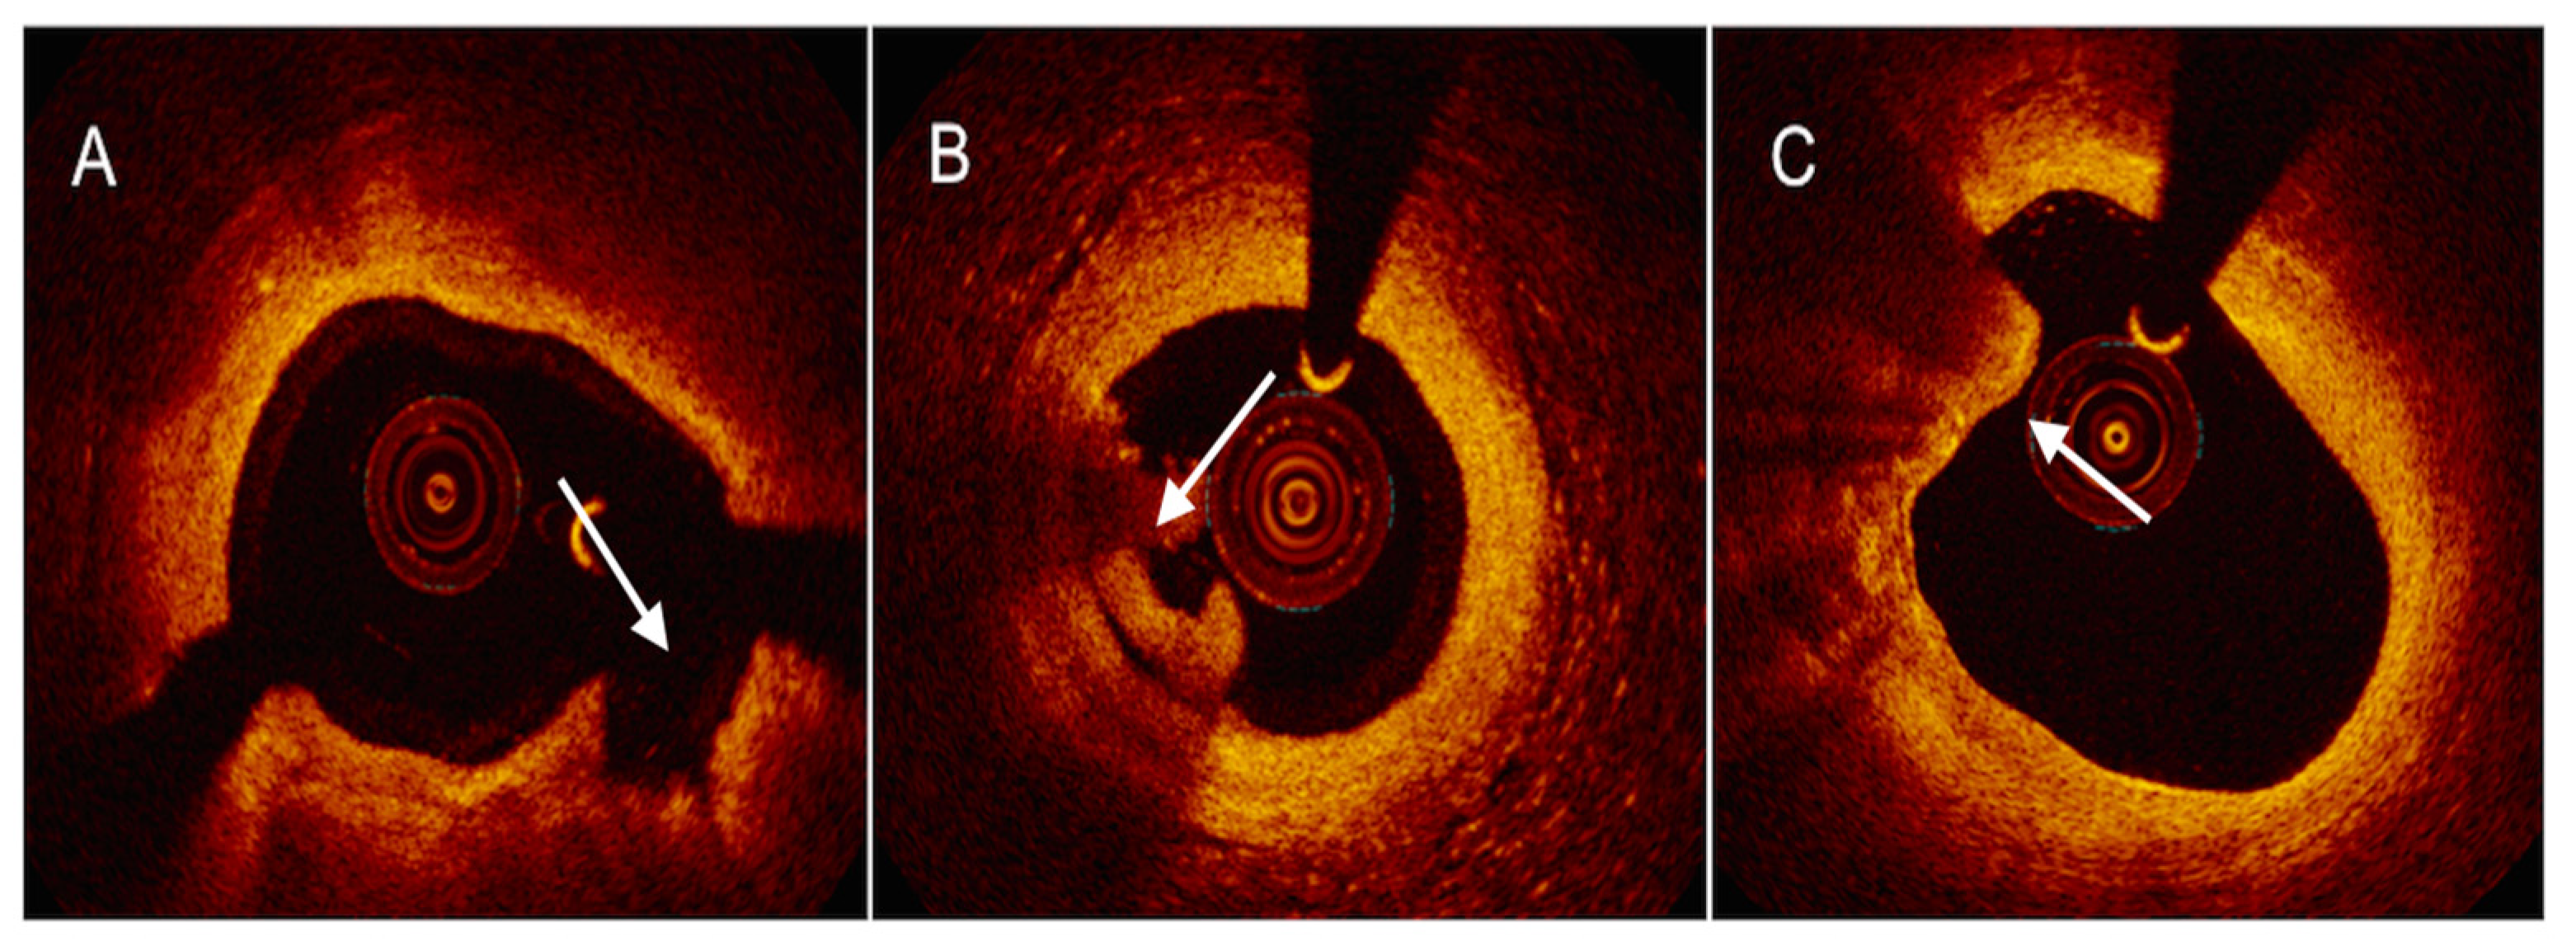

- Xing, L.; Yamamoto, E.; Sugiyama, T.; Jia, H.; Ma, L.; Hu, S.; Wang, C.; Zhu, Y.; Li, L.; Xu, M.; et al. EROSION Study (Effective Anti-Thrombotic Therapy Without Stenting: Intravascular Optical Coherence Tomography-Based Management in Plaque Erosion): A 1-Year Follow-Up Report. Circ. Cardiovasc. Interv. 2017, 10, e005860. [Google Scholar] [CrossRef]